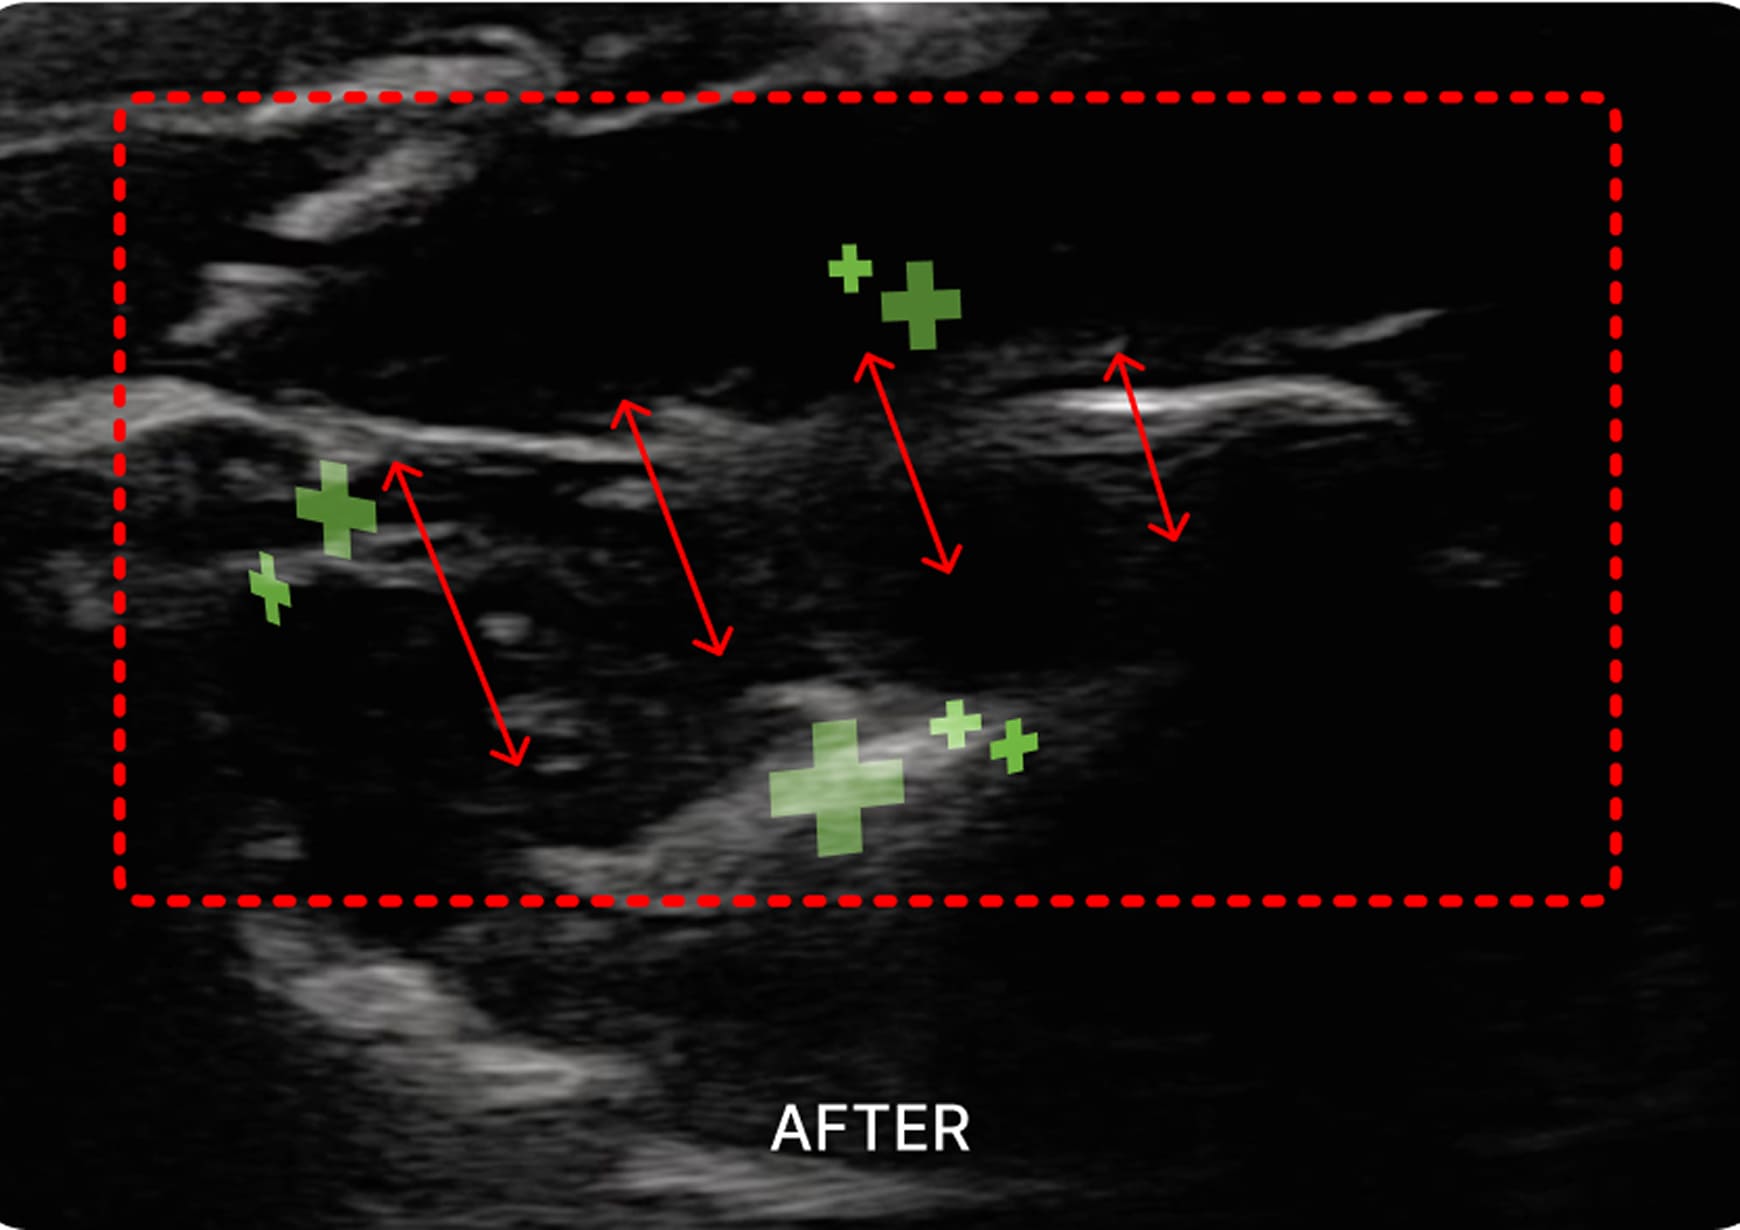

초음파 검사

1. 초음파 시술

초음파를 활용하여 근육과 신경 문제를

정확히 진단하고 치료하여 통증과 기능

이상을 개선하는 시술입니다.

외익돌근

턱의 움직임에 관여하는 심부 근육문제를 해결하여

턱관절 장애, 안면 비대칭, 편두통 등을 완화합니다.